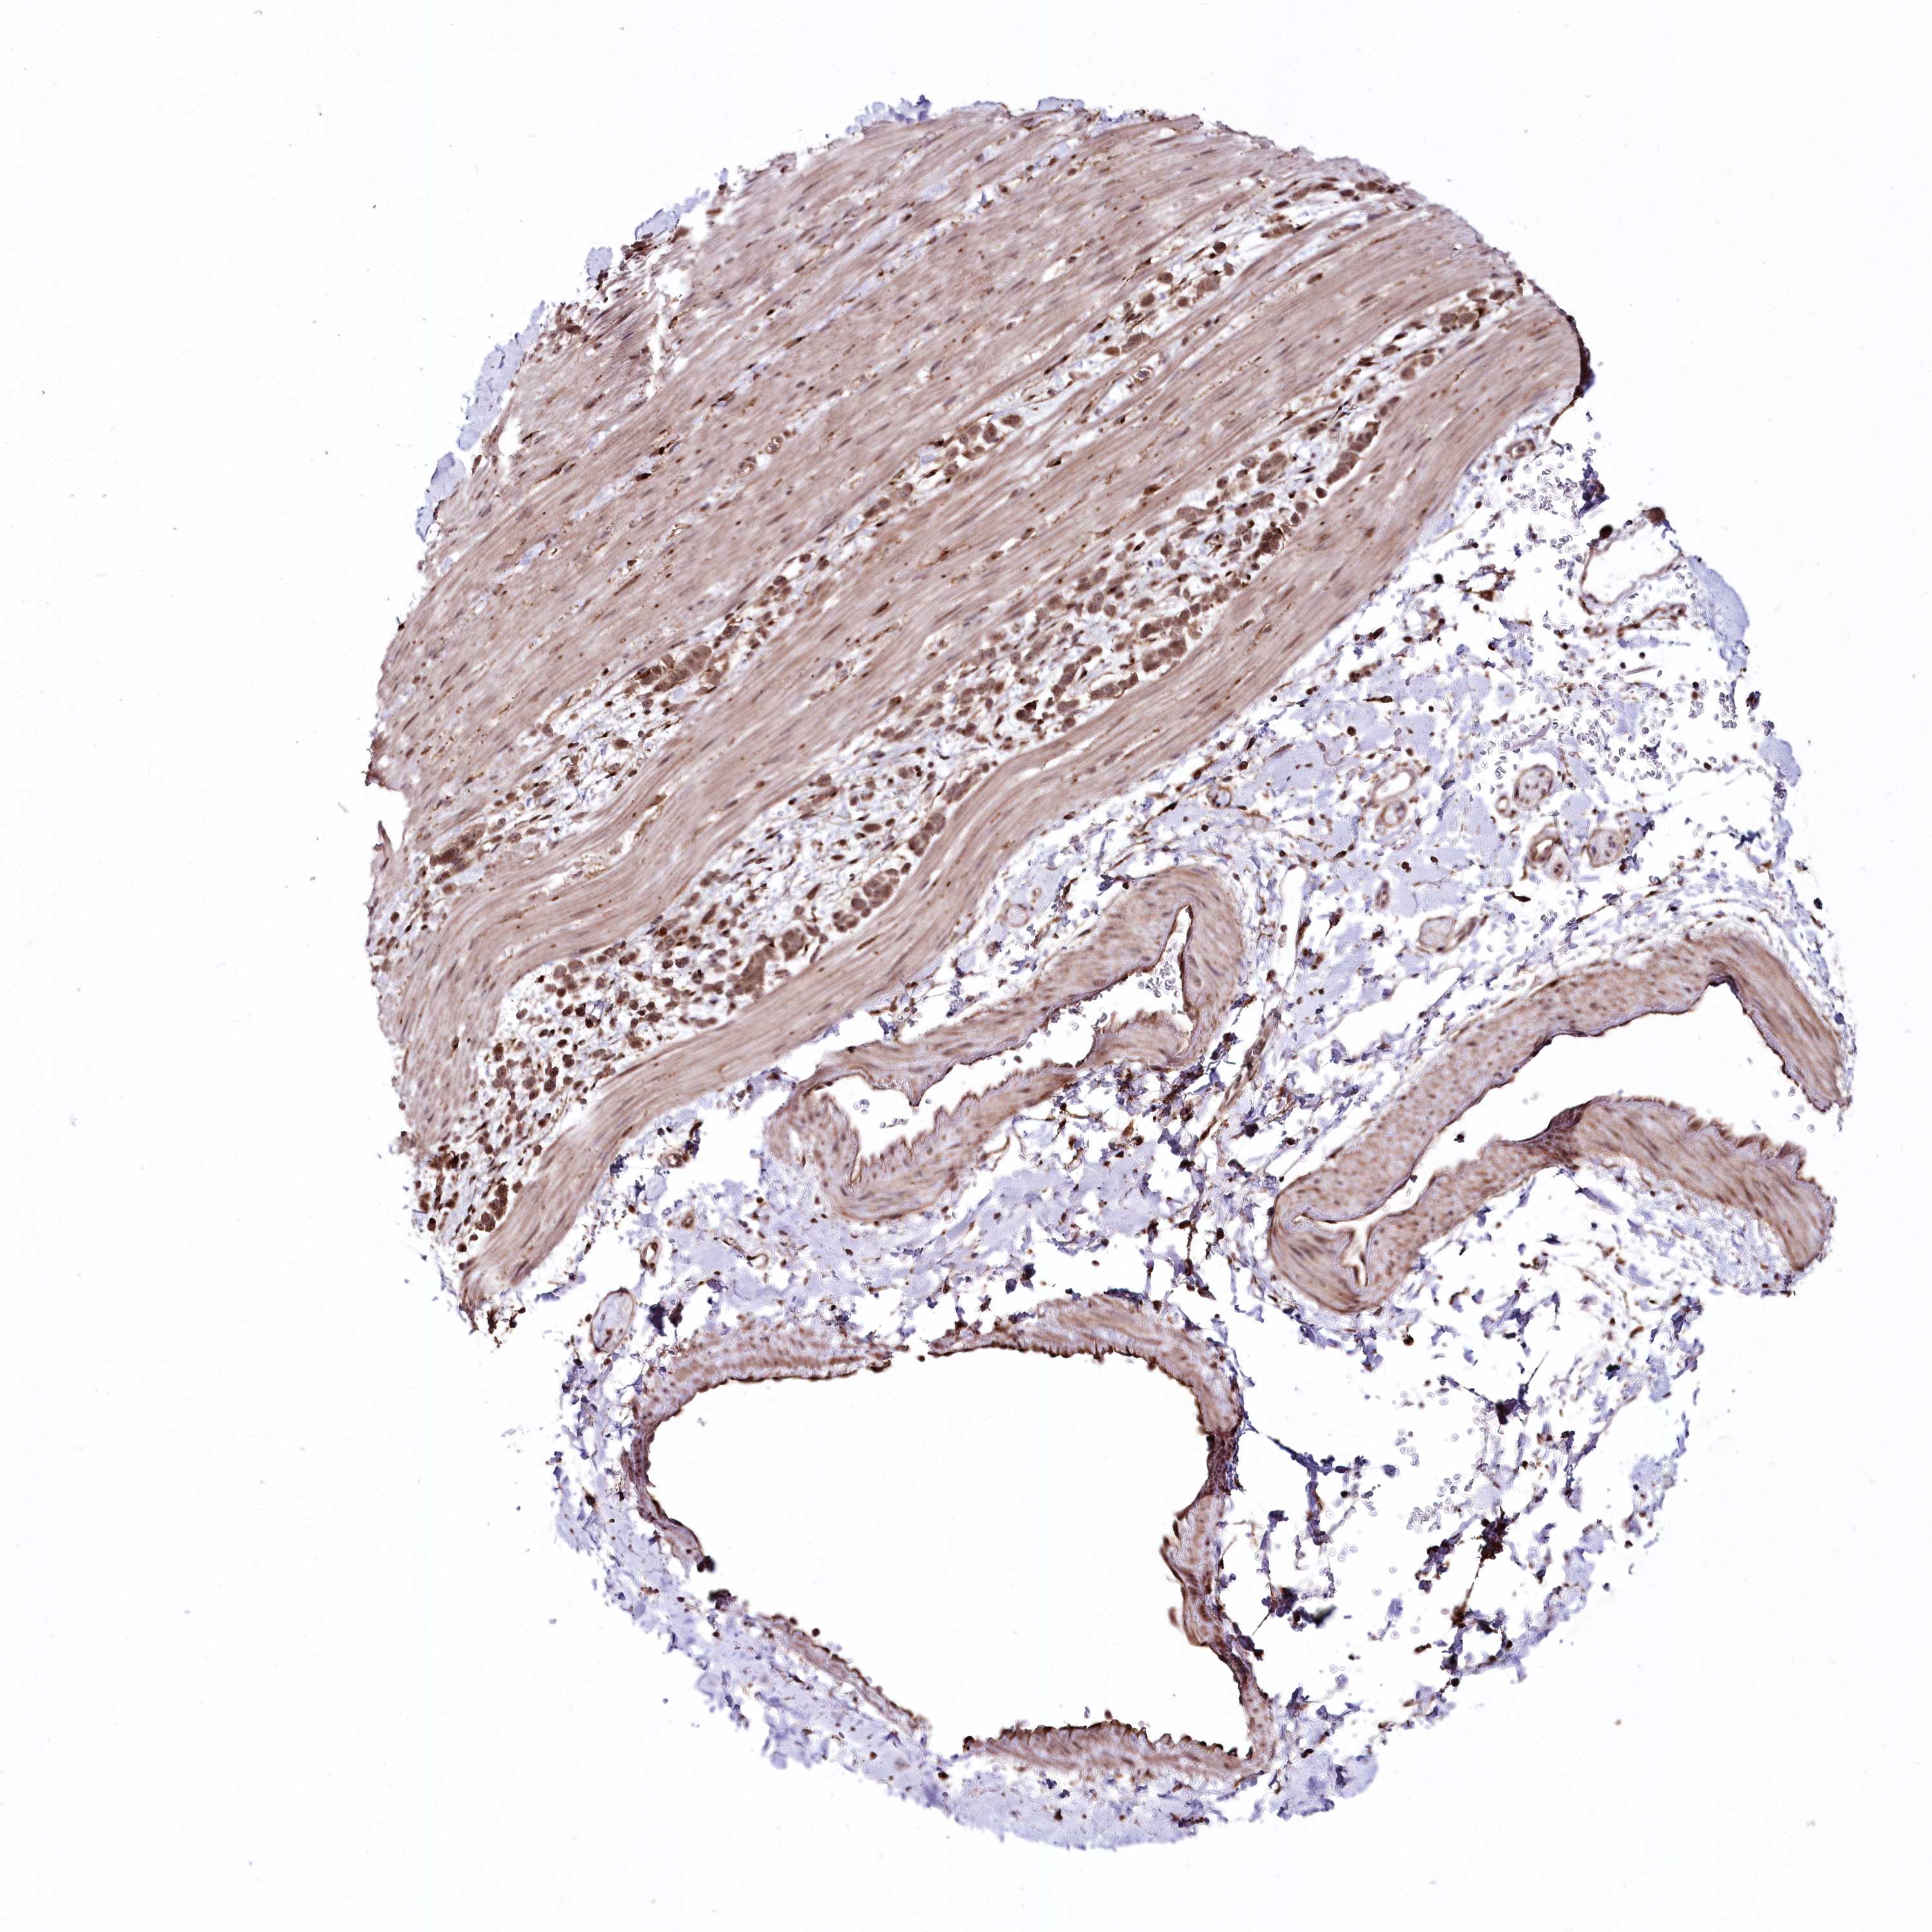

PANCREATIC CANCER - Protein expressioni

A mouse-over function shows sample information and annotation data. Click on an image to view it in a full screen mode. Samples can be filtered based on level of antibody staining by selecting one or several of the following categories: high, medium, low and not detected. The assay and annotation is described here.

Note that samples used for immunohistochemistry by the Human Protein Atlas do not correspond to samples in the TCGA dataset.

Antibody stainingi

Antibody staining in the annotated cell types in the current human tissue is reported as not detected, low, medium, or high, based on conventional immunohistochemistry profiling in selected tissues. This score is based on the combination of the staining intensity and fraction of stained cells.

Each image is clickable and will lead to virtual microscopy that enables deeper exploration of all samples and also displays staining intensity scores, fraction scores and subcellular localization as well as patient and tissue information for each sample.

Antibody HPA028911

Antibody CAB037020

Staining

High

Medium

Low

Not detected

Intensity

Strong

Moderate

Weak

Negative

Quantity

>75%

75%-25%

<25%

None

Location

Nuclear

Cytoplasmic/membranous

Cytoplasmic/membranous,nuclear

Adenocarcinoma, NOS